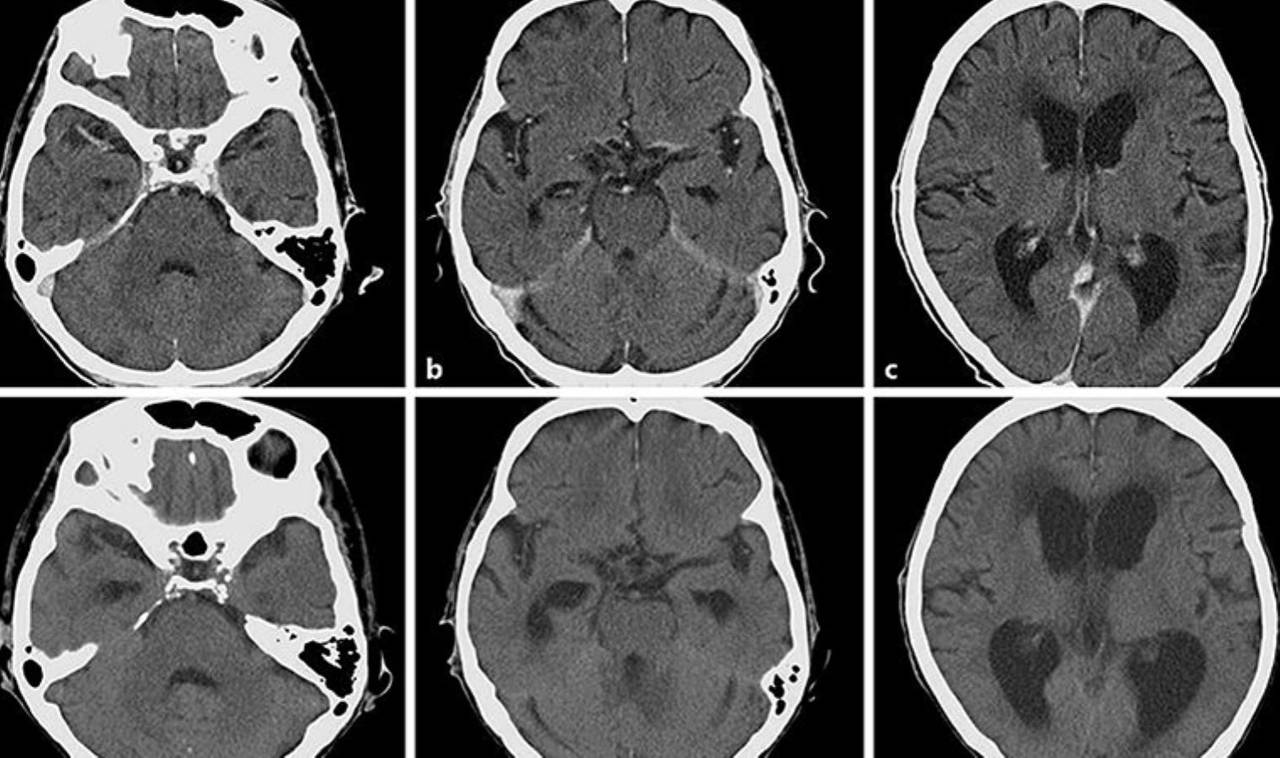

BEYİN KANSERİNE ETKİLİ

Artemisia annua'dan elde edilen Arteannuin B adlı bileşiğin, glioblastoma hücreleri olarak bilinen kötü huylu beyin kanseri hücrelerine karşı etkili olduğu gözlemlenmiştir. Bu bileşik, kanser hücrelerinin aşırı eksprese ettiği sistein proteazlarını inhibe edebilir. Bu da kanser hücrelerine karşı etkinliğini artırır.